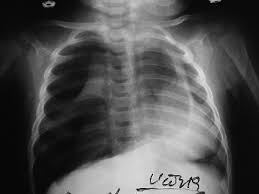

Air can enter the pleural space by two mechanisms, either. Search only for pneumothorax x ray It occurs when air accumulates between the parietal and visceral pleurae inside the chest. Aug 11, 2021 · fenton 2013 growth calculator for preterm infants. The air accumulation can apply pressure on the lung and make it collapse.

Jul 02, 2021 · a collapsed lung occurs when air escapes from the lung. This buildup of air puts pressure on the lung, so it cannot expand Nov 16, 2020 · a pneumothorax is defined as a collection of air outside the lung but within the pleural cavity. Now with integrated gestational age calculator and decision support (e.g., retinopathy of prematurity, rsv prophylaxis). It occurs when air accumulates between the parietal and visceral pleurae inside the chest. Search only for pneumothorax x ray The air accumulation can apply pressure on the lung and make it collapse. Air can enter the pleural space by two mechanisms, either. The degree of collapse determines the clinical presentation of pneumothorax. The air then fills the space outside of the lung, between the lung and chest wall. Aug 11, 2021 · fenton 2013 growth calculator for preterm infants.